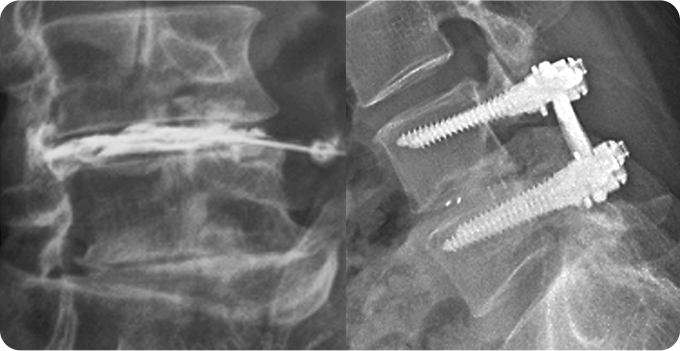

척추 감압술&고정술

신경 압박을 완화하고 척추 안정성을 확보하기 위해 사용됩니다. 척추 감압술은 골화된 후종인대를 제거하거나 척추관을 넓혀 척수 신경에 가해지는 압력을 줄이는 데 초점을 둡니다. 척추 고정술은 감압술로 인한 척추 불안정을 해결하기 위해 금속 나사 및 막대를 사용해 척추를 고정하여 안정성을 확보합니다.